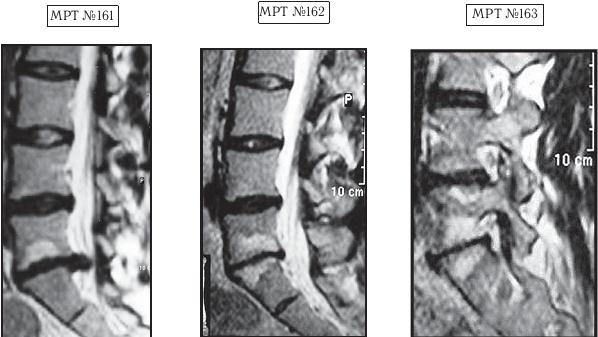

На МРТ № 161 наблюдается поясничный отдел позвоночника: секвестрированная грыжа межпозвонкового диска в сегменте LV-SI, абсолютный стеноз позвоночного канала. Светлый участок на теле позвонка LV — жировая дегенерация ткани.

На МРТ № 162 наблюдается поясничный отдел позвоночника после двух курсов лечения методом вертеброревитологии: отсутствие грыжи межпозвонкового диска в сегменте LV-SI, отсутствие стеноза позвоночного канала, стабильное состояние практически полностью утилизированного диска в сегменте LV-SI.

На МРТ № 163 наблюдается поясничный отдел позвоночника после двух курсов лечения методом вертеброревитологии: восстановление биомеханики позвоночника, нормальное соотношение дугоотростчатых суставов, фораминальные отверстия в норме.